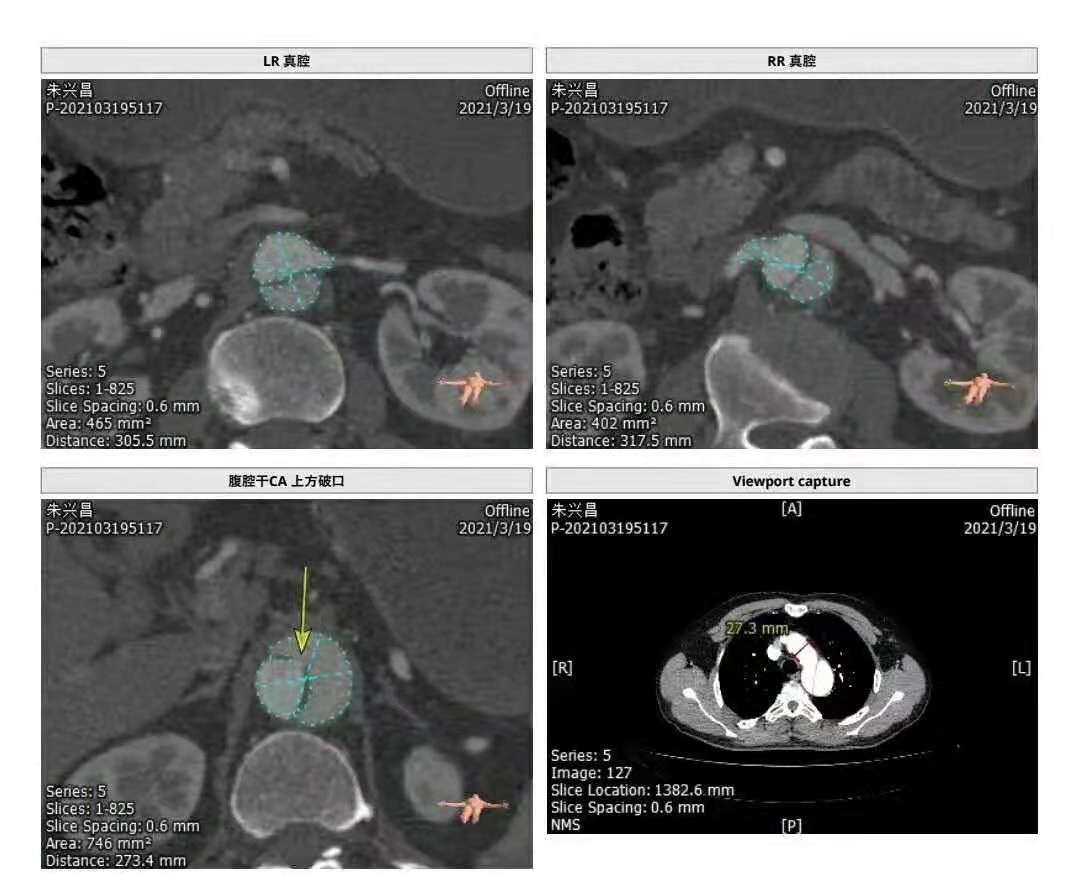

患者男性,67歲,因咳嗽、胸部不適就醫(yī),CT檢查提示主動(dòng)脈夾層(B型)、主動(dòng)脈弓及腹主動(dòng)脈硬化,局部形成鈣化斑塊,隨以“主動(dòng)脈夾層瘤”急診收住。

時(shí)間就是生命,我院立即開辟綠色通道,以最快捷、最高效的就診流程,積極完善術(shù)前準(zhǔn)備,在局部麻醉下經(jīng)腹股溝股動(dòng)脈穿刺行“主動(dòng)脈夾層腔內(nèi)修復(fù)術(shù)”。西安交大一附院血管外科專家、主任醫(yī)師馮駿教授親臨指導(dǎo),手術(shù)順利,破口封閉,血管真腔開通,整個(gè)手術(shù)過程歷時(shí)約30分鐘,患者生命體征穩(wěn)定,術(shù)中、術(shù)后未訴不適;術(shù)后第二天,患者可下床活動(dòng);術(shù)后第三天,患者康復(fù)出院。